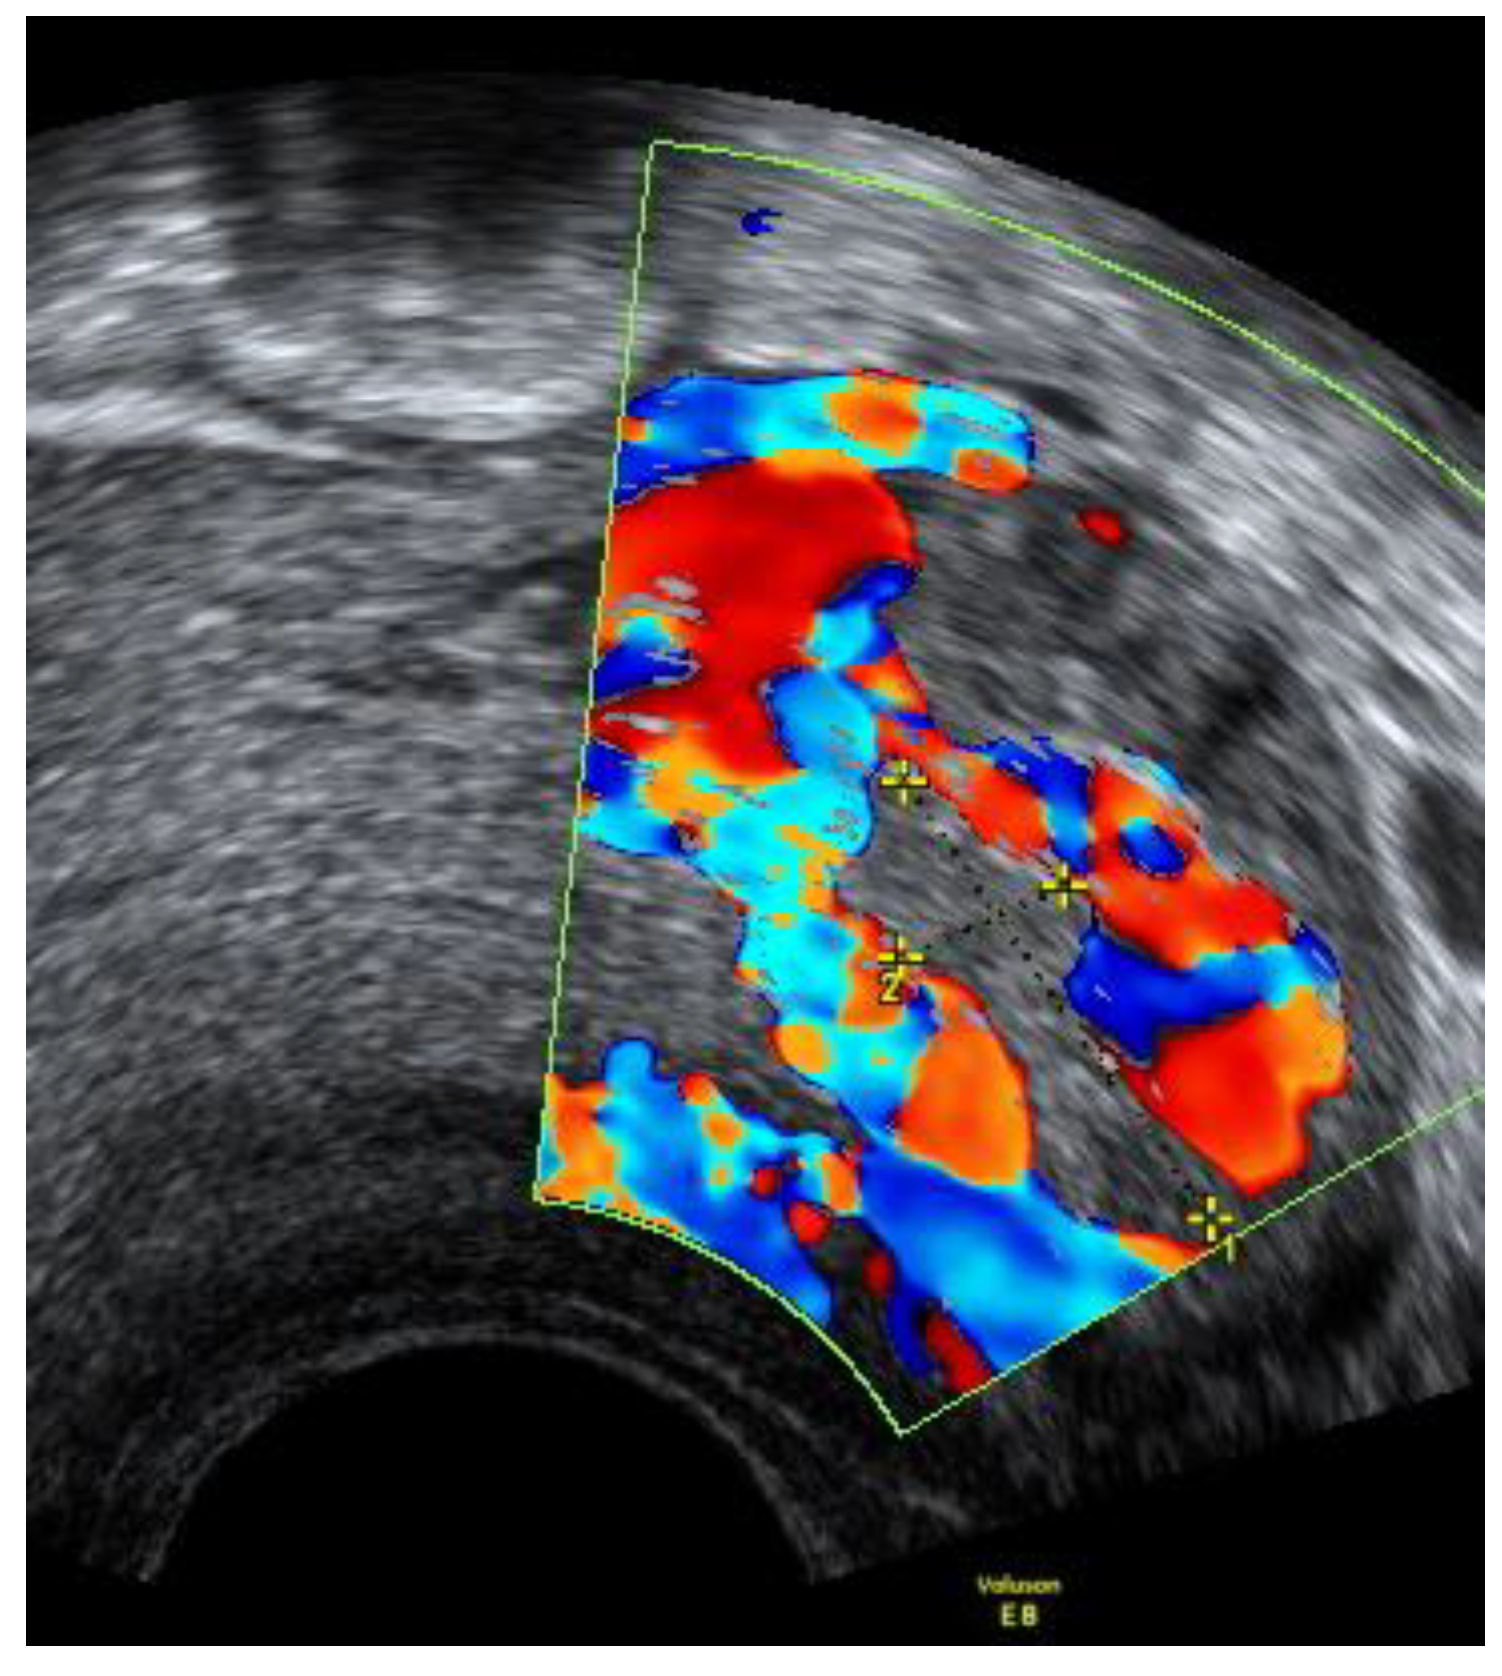

On the 22nd week of gestation, the woman was admitted to tertial level hospital complaining of pain in hypogastric and left iliac regions of the abdomen, provoked by physical exercise. Ultrasonography was performed, the remaining unchanged mass in the left cornu of the uterus was observed as well as an intraamniotic septum in the lower segment of the uterus, as shown in Figure 5 and Figure 6. The fetal growth of the intrauterine pregnancy was unaffected and matched its gestational age. Conservative treatment was chosen, the pain resolved and the patient was discharged in 2 days.

Figure 6. Left cornu of the uterus visualized by 3D transabdominal ultrasonography at the 22nd week of gestation.